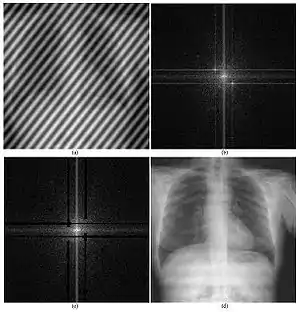

An important application of information engineering in medicine is medical signal processing.[1] It refers to the generation, analysis, and use of signals, which could take many forms such as image, sound, electrical, or biological.[25]

Medical image computing and imaging informatics

Imaging informatics and medical image computing develops computational and mathematical methods for solving problems pertaining to medical images and their use for biomedical research and clinical care. Those fields aims to extract clinically relevant information or knowledge from medical images and computational analysis of the images. The methods can be grouped into several broad categories: image segmentation, image registration, image-based physiological modeling, and others.